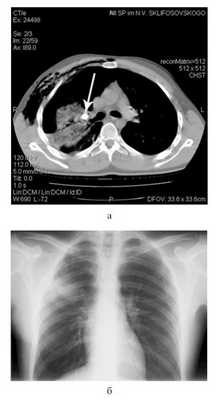

В связи с большим поступлением воздуха по дренажу сразу после этой операции пострадавшему выполнена КТ груди (рис. 6, а): Рисунок 6. Данные обследования пострадавшего Ш. а - компьютерная томограмма перед операцией; б - обзорная рентгенограмма груди перед выпиской из стационара. имелось инородное тело (пуля) в прикорневых отделах правого легкого, сдавливающее просвет верхнедолевого бронха. Травматическая инфильтрация II, III, VI, VII, VIII, IX, X сегментов правого легкого на фоне частичного коллабирования. Несмотря на наличие плеврального дренажа (по Бюлау), на фоне незначительного гемоторакса (230 см 3 ) имелся пневмоторакс большого объема (1100 см 3 ). Определялись эмфизема мягких тканей правой поверхности грудной стенки, перелом II и III ребер справа.